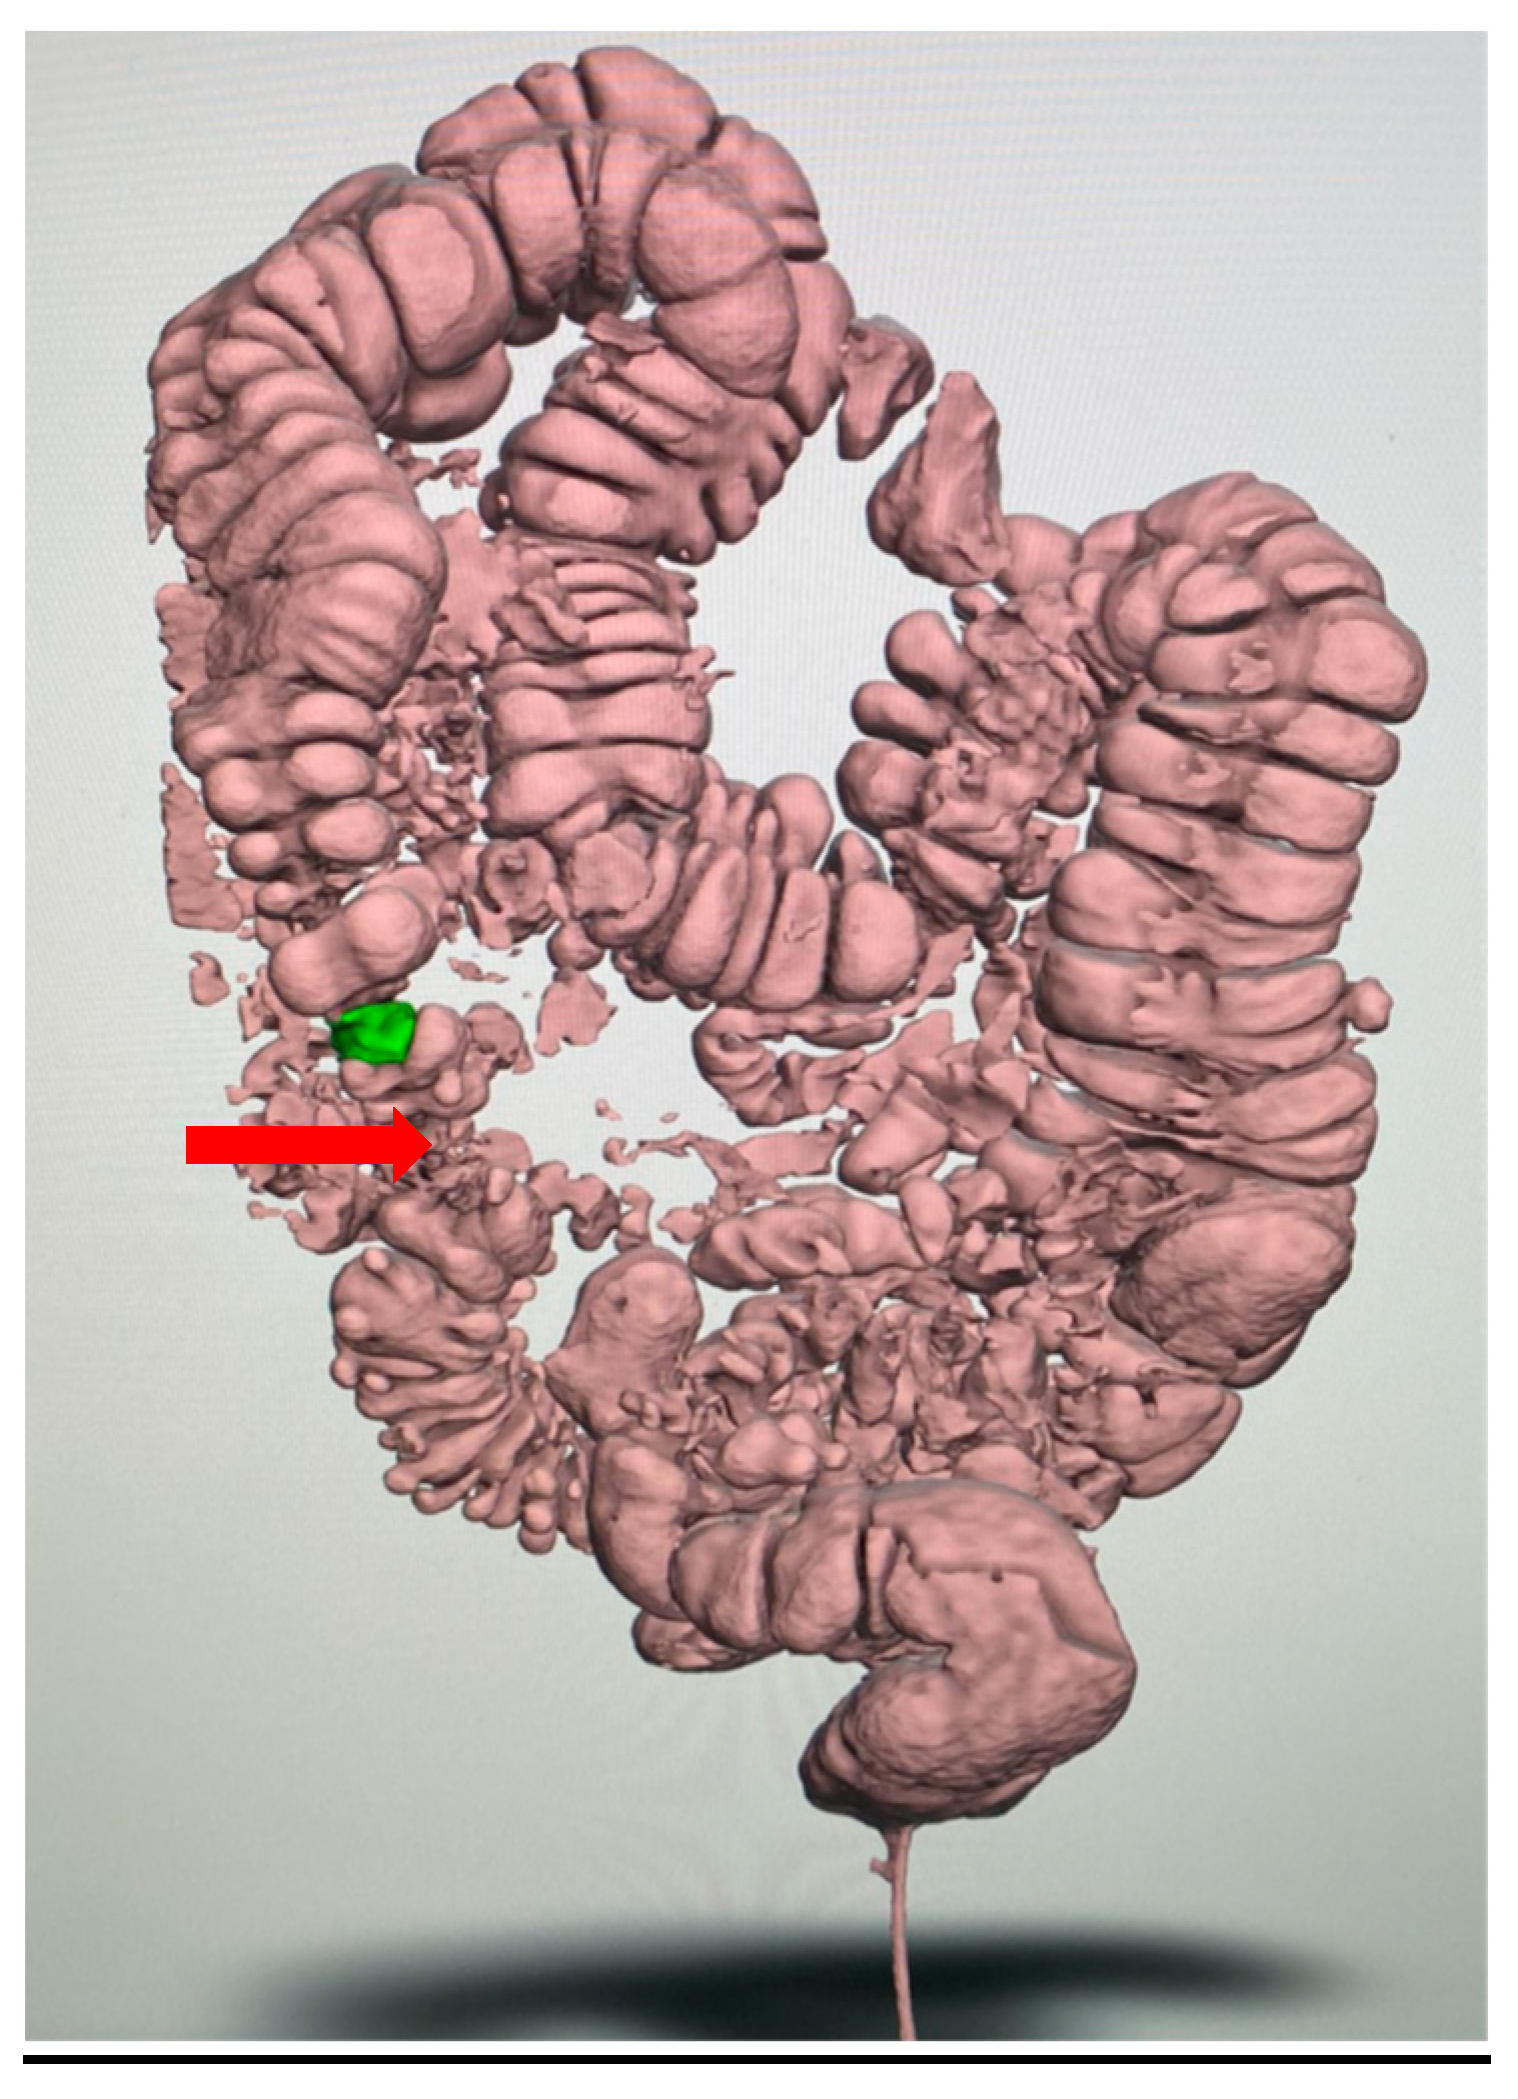

| Extent of diverticulosis | Massive diverticulosis of sigmoid and descending colon | Same finding confirmed with clearer visualization of segmental involvement |

| Stenotic area | Suspected narrowing, poorly defined | Stenotic segment clearly delineated, with precise localization and extension |

| Anatomical relationships | Limited perception of spatial relations | Improved understanding of relationship between diseased colon and surrounding structures |

| Surgical planning implications | Suggestive of need for resection | Supported decision for left hemicolectomy |

| Tactile/spatial perception | 2D visualization only | Physical 3D model provided tactile and spatial feedback useful for team discussion and planning |